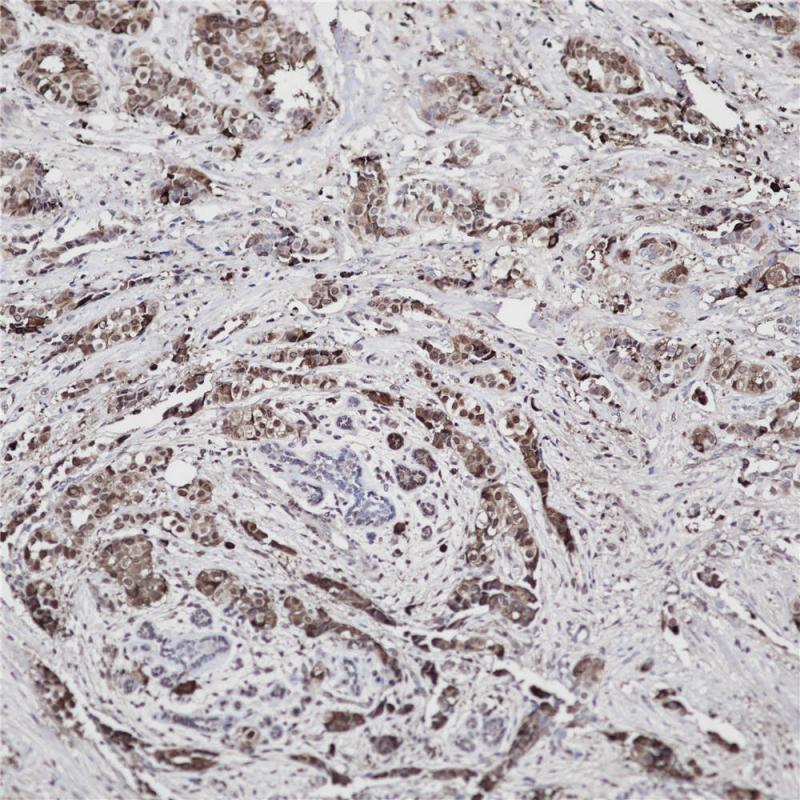

Mammaglobin 重组兔单克隆抗体

Mammaglobin 也称乳腺珠蛋白,是一种特异地表达于乳腺上皮细胞、原发性乳腺癌组织的分泌性球蛋白。该抗体具有极强的乳腺组织特异性,在正常淋巴结和非乳腺癌转移淋巴结中一般均不表达,能较好地诊断乳腺癌淋巴结微转移。

阳性对照

乳腺癌

亚细胞定位

细胞质